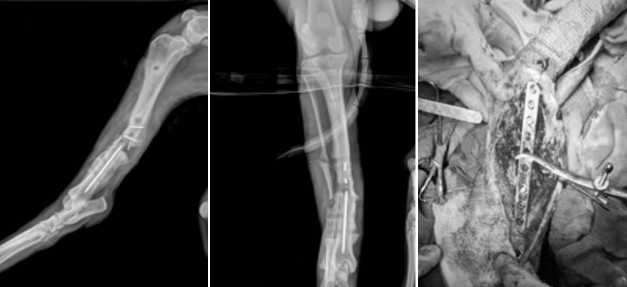

宋火松院长接诊过一例极具挑战性的骨科病例——一只3岁多的萨摩耶犬“暴雪”,其右侧胫骨骨折,虽经三次手术干预,仍未能实现骨愈合,发展为复杂的陈旧性骨折。

该病例的骨科治疗面临严峻挑战:骨折断端存在明显骨缺损,周围形成肥厚性骨痂,同时伴有骨轴线对位不齐,这些因素共同导致骨愈合环境极差,传统固定方式难以奏效。

面对这一难题,宋火松院长制定了系统性的“翻修”手术方案。手术采用胫骨内侧入路,在清理骨折断端间填充的软组织后,首先使用克氏针在断端钻孔创造新鲜化界面,随后将块状与颗粒状骨修复材料精准填充于骨折间隙,最后以引导补片完整包裹材料及断端区域,为骨再生构建了稳定的生物学环境,并辅以胫骨内侧骨板提供坚强固定。

患犬在术后第三天即实现负重行走。系列X线评估显示,术后4周骨缺损明显缩小,骨间隙出现连续骨组织连接;6周时骨折线趋于模糊;至12周时骨折线完全消失,实现了影像学与临床上的双重愈合。

这一成功案例充分展现了宋火松院长在复杂骨科翻修手术中的精湛技艺,其通过先进骨修复材料的创新应用与生物力学固定的完美结合,为顽固性骨折不愈合提供了有效的解决方案,标志着其在骨科重建领域的技术高度。